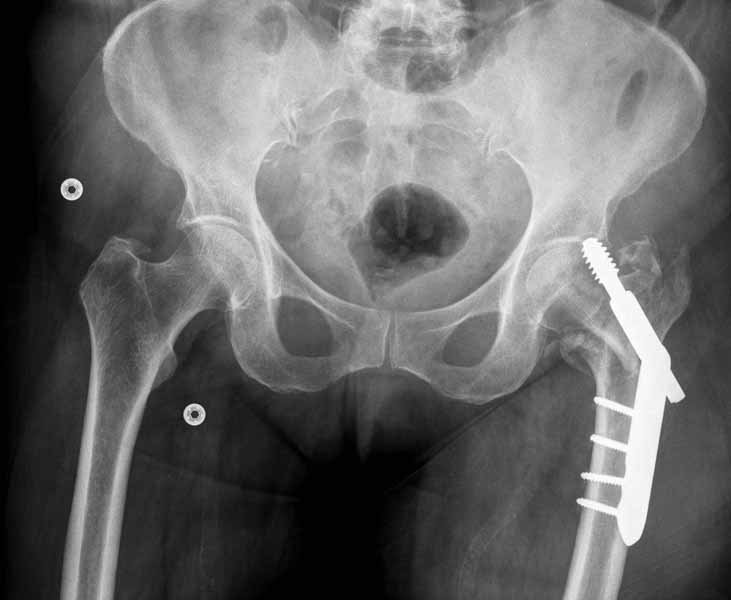

Прилагаю снимок сделанный еще в стационаре через 2 недели после операции.

Кстати, я придерживаюсь мнения проводить шеечный шуруп через calcar - как самый прочный участок, сзади-снизу шейки. Есть мнения что лучше по центру - избежать эксцентрических сил и момента. По-моему трудно определить центр вращения (а может он уже определен) в плече бедра и шейке. Если calcar - это самое прочное место, то скорее всего это и есть центр нагрузки и ось вращения. Идея позиции перед передним кортексом - интересная, требует обдумывания.